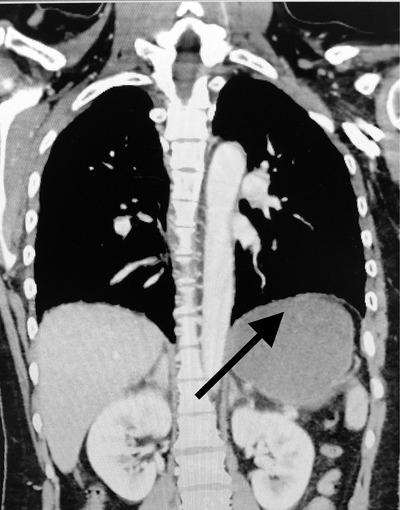

Woman with nausea and abdominal pain after a motor vehicle collision.